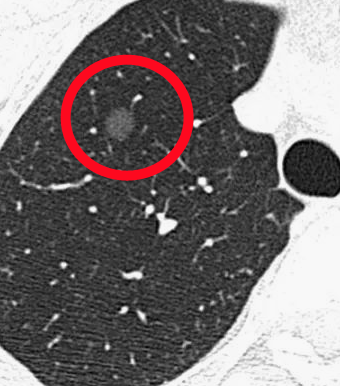

病例2:胸部摄片未见明显异常。

病例2:胸部摄片未见明显异常,

但CT扫描发现右肺结节,

术后病理检查:原位腺癌